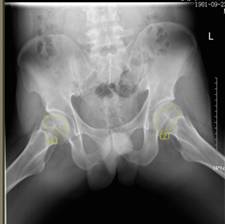

37歲的患者吳先生反復(fù)雙髖疼痛2月余,聽說瀘州市中醫(yī)院在治療骨科疾病方面很有經(jīng)驗(yàn),遂來到醫(yī)院治療。經(jīng)檢查,吳先生雙側(cè)股骨頭壞死(II期),如不及時(shí)進(jìn)行手術(shù)治療,他的股骨頭將進(jìn)一步壞死至骨頭塌陷,引發(fā)關(guān)節(jié)炎,嚴(yán)重時(shí),必須行關(guān)節(jié)置換術(shù)。這樣,將會(huì)給吳先生的生活質(zhì)量及經(jīng)濟(jì)帶來嚴(yán)重負(fù)擔(dān)。

術(shù)前報(bào)告顯示患者雙側(cè)股骨頭壞死